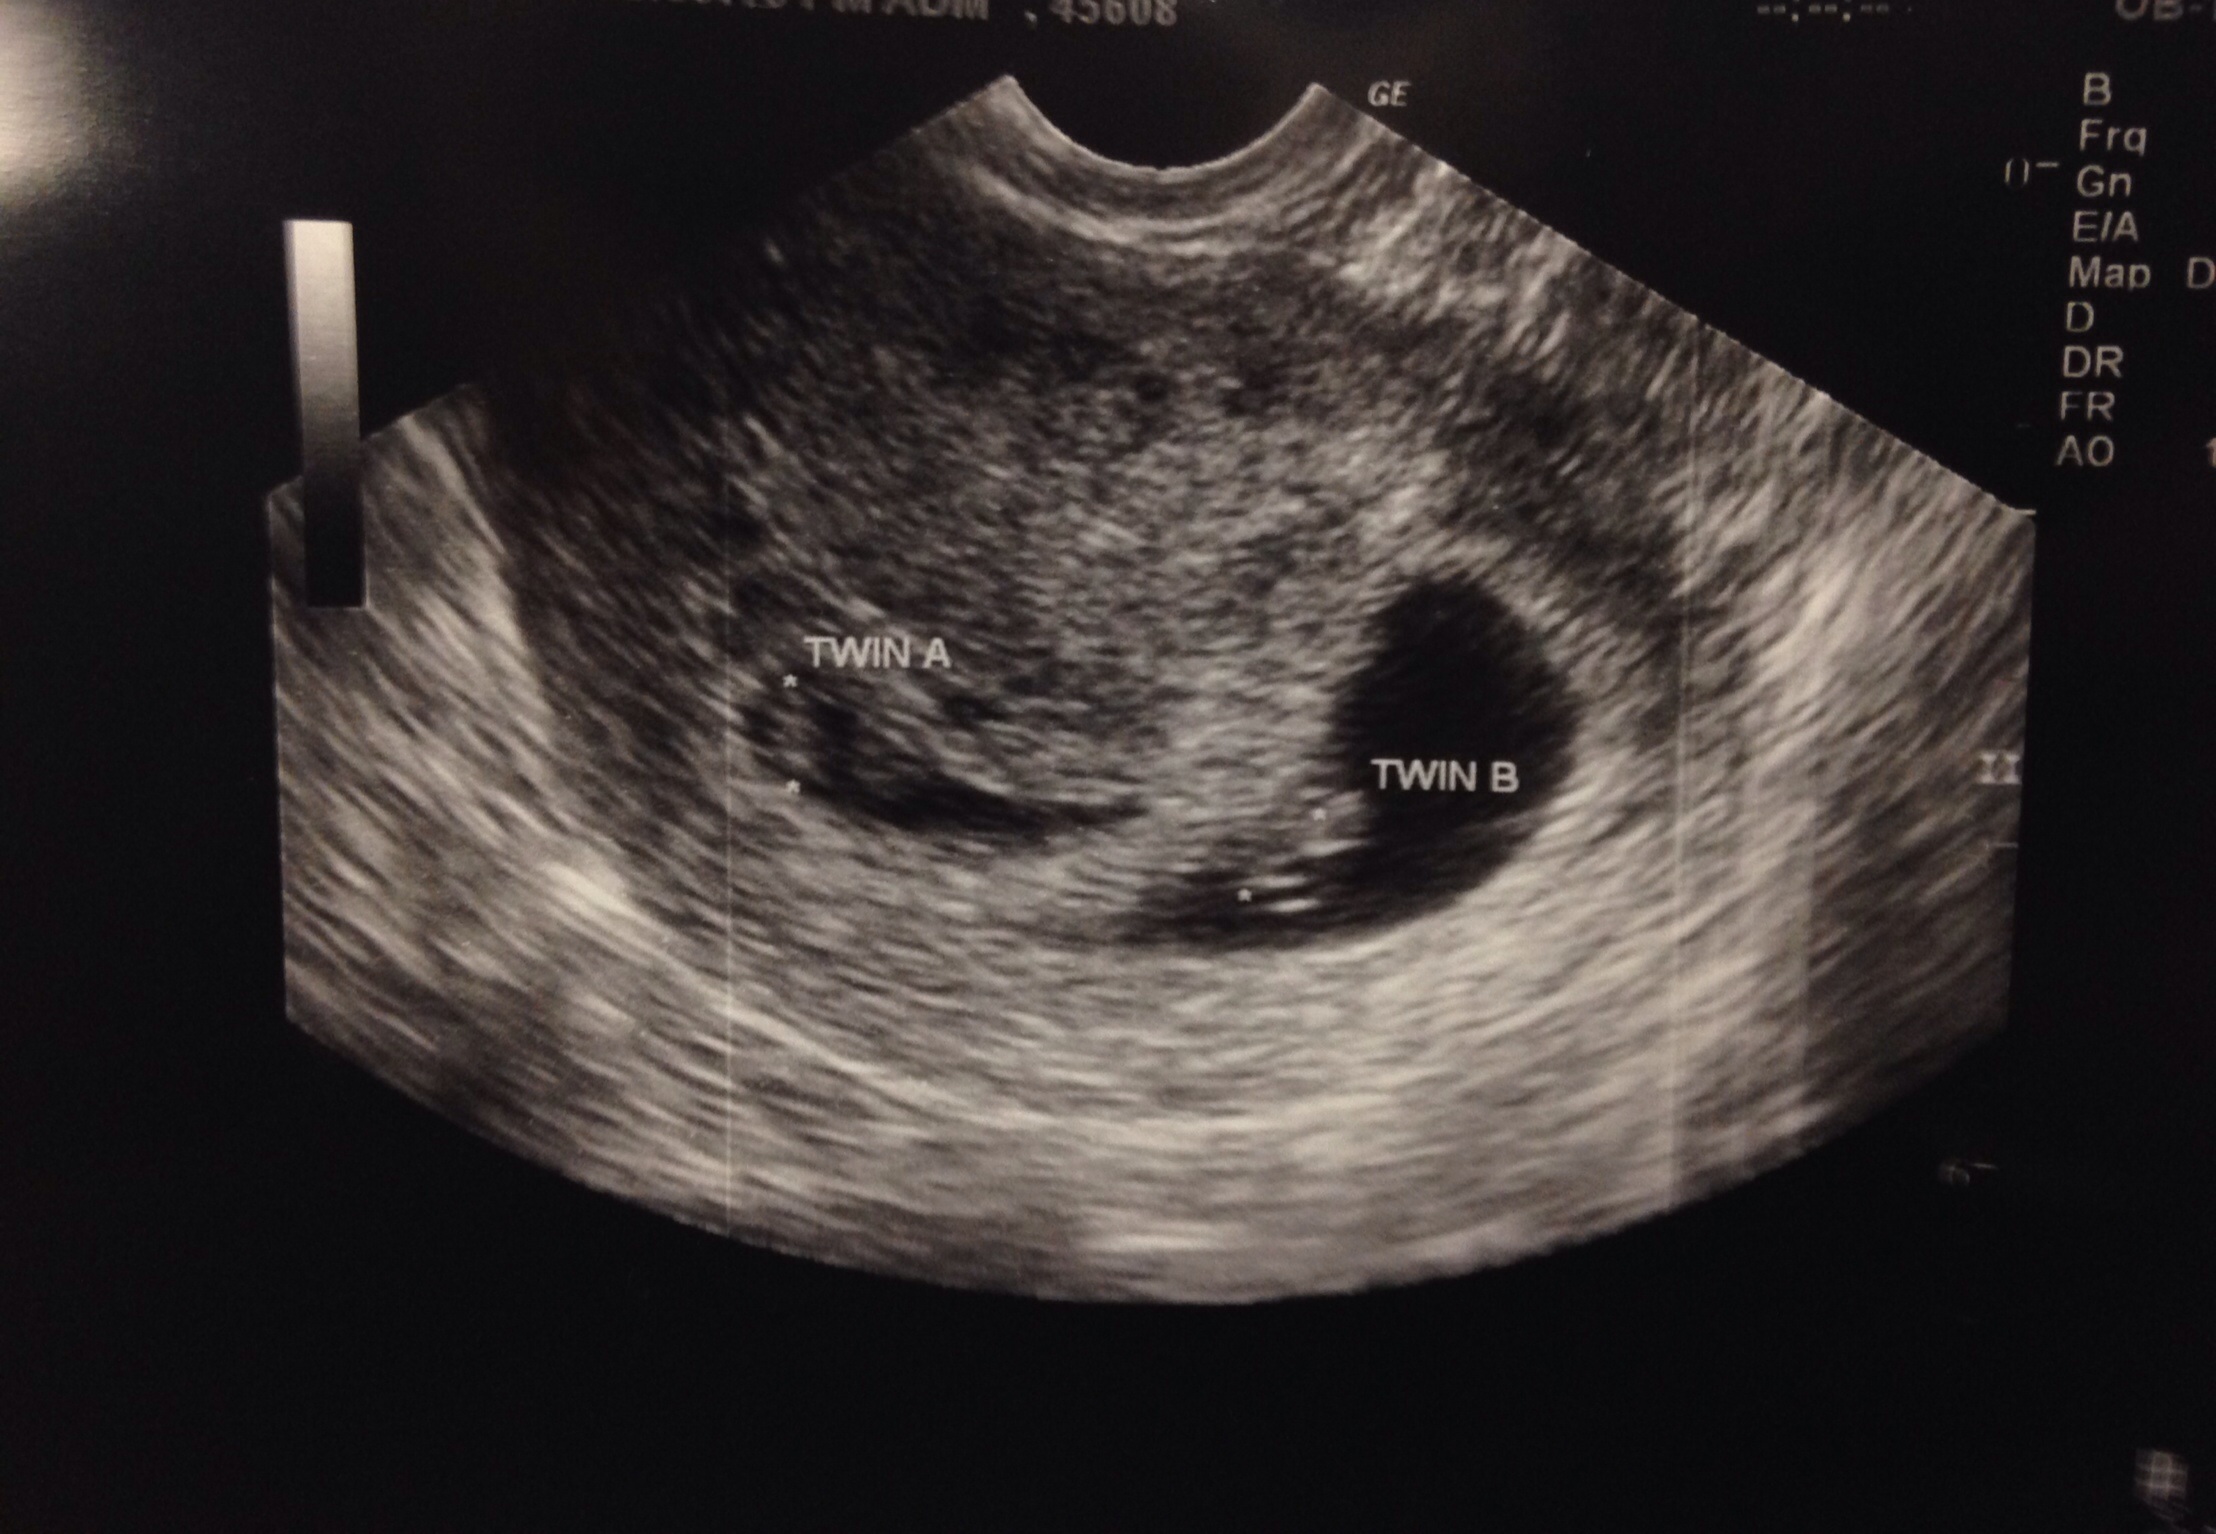

Hey all! My babies are a result of clomid. Is it more likely they are fraternal? Looks like two sacs and there were definitely two placenta. But the doctor only saw one corpus luteum. Could it be too early? Posted in my March thread also but figured you ladies may have some more insight :)!

• I'm 7 weeks 2 days. Could one of the corpus luteum have absorbed? Do we agree it's two sacs? Definitely two placenta but doctor was weary to say "two sacs" since he said it was early and lining could thin. But goodness they sure do look like two separate sacs

• If there are two placentas, there are definitely two sacs.

And everything that @AshB62‌ said. My di/di boys are most definitely fraternal.

Your pictures look like di/di twins to me, but I'm no doctor.